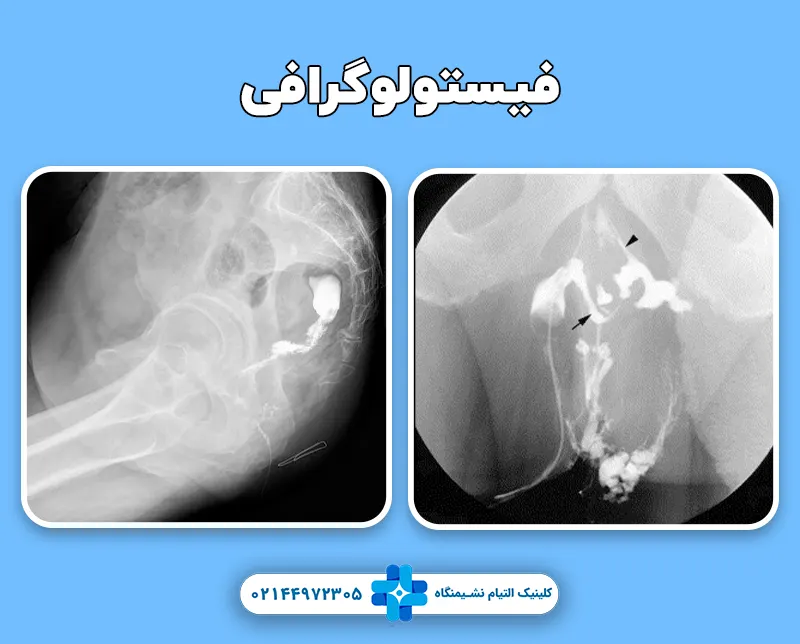

فیستولوگرافی یک روش تصویربرداری جهت تشخیص و بررسی فیستول هایی است که در ناحیه مقعد بروز می کنند. این تکنیک در واقع برای بررسی مسیرهای فیستول مورد استفاده قرار می گیرد. فیستول مجرایی غیر طبیعی است که یک اندام داخلی را به اندام دیگر یا به پوست متصل کنند. فیستول می تواند در هر قسمتی از بدن ایجاد شود، اما بسیاری از آنها در ناحیه روده ها و مقعد خصوصا در صورت ابتلا به بیماری های التهابی روده ایجاد می شوند.

رادیولوژیست در حین عبور رنگ از فیستول، چندین مرتبه تصویر برداری انجام می دهد. این کار به شناسایی مجاری فیستول و جهت درمان بهتر آن کمک خواهد کرد. عمل فیستولوگرافی معمولاً حدود 30 تا 60 دقیقه طول می کشد.

تصاویری که با این روش به دست می آید کیفیت بالایی دارند در نتیجه پزشک به راحتی می تواند مجاری فیستول را تشخیص دهد. علاوه بر این شدت اشعه ای که در این تصویر برداری در معرض آن قرار می گیرد بسیار کم است بنابراین باعث آسیب هایی مانند سرطان نخواهد شد. برای فیستولوگرافی آمادگی خاصی نیاز ندارید فقط کافی است چند ساعت قبل آن از مصرف خوراکی ها و آشامیدنی ها خودداری کنید و پزشک را از بیماری ها و آلرژی های خود مطلع کنید.